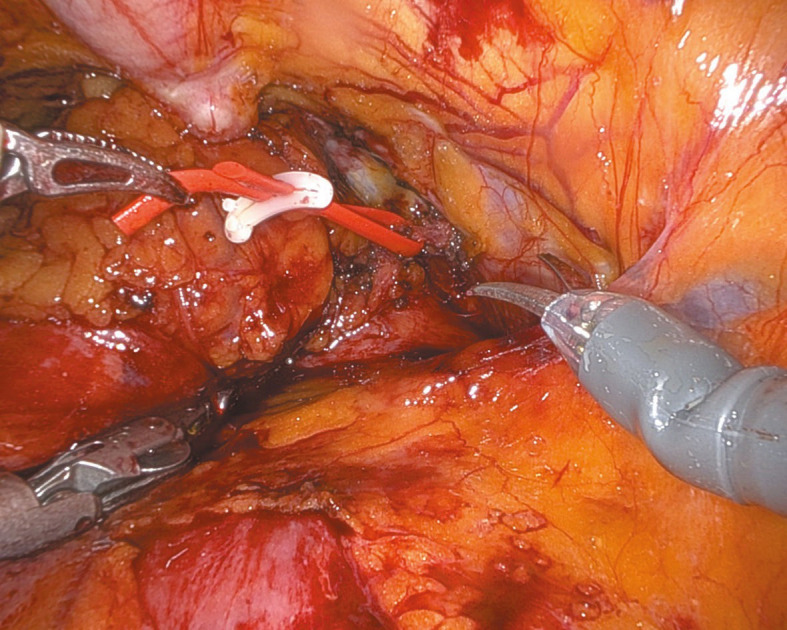

机器人辅助手术治疗中尿道吊带(MUS)糜烂进入膀胱代表了泌尿外科的一种新方法。本研究报告了波兰使用经腹膜机器人广泛入路进行全网切除(TREATME)的前2例病例。两种手术均成功完成,完全去除补片。没有发生手术内或术后并发症,也不需要转开手术。这些初步发现表明,治疗可能是治疗复杂MUS并发症的可行和安全的选择,需要在更大规模的研究中进一步评估。

Robot‑assisted surgical management of mid‑urethral sling (MUS) erosion into the bladder represents a novel approach in urological surgery. This study reports the first 2 cases in Poland treated using the transperitoneal robotic extensive approach for total mesh excision (TREATME). Both procedures were performed successfully, with complete mesh removal. No intra‑ or postoperative complications occurred, and conversion to open surgery was not required. These initial findings suggest that TREATME may be a feasible and safe option for managing complex MUS complications, necessitating further evaluation in larger studies.